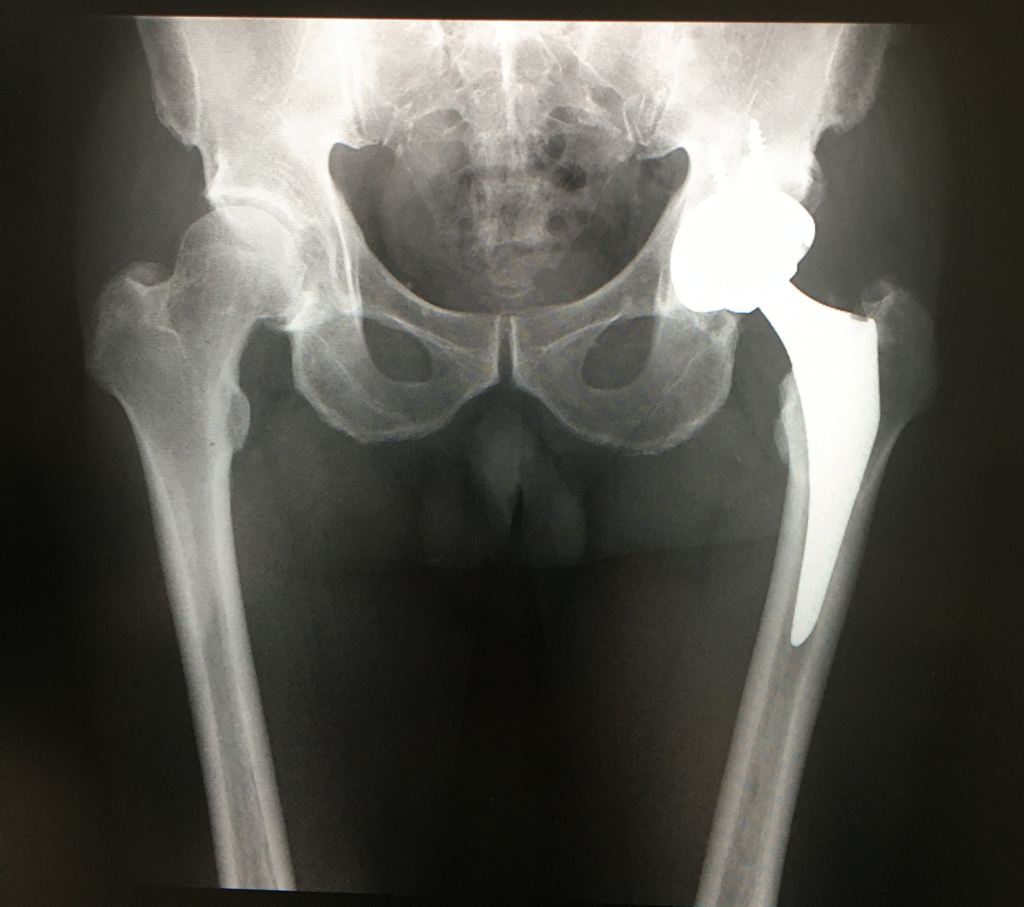

こちらは、79歳の空手の形(かた)の師範です。仰臥位前外側アプローチ(ALS THA)で左側に人工股関節を設置しました。

動画を見ると、股関節の動きが重要となる形(かた)も、難なく動けていることがわかります。

術後3ヶ月で復帰し、今日も門弟への指導に励みます。

脱臼リスクが少ない手術方法、仰臥位前外側アプローチ(ALS THA)を検討している方は、ご相談に乗りますので、ご連絡ください。人工股関節専門ドクター・久留隆史医師がご回答致します。板橋中央総合病院にて外来受診可能です。